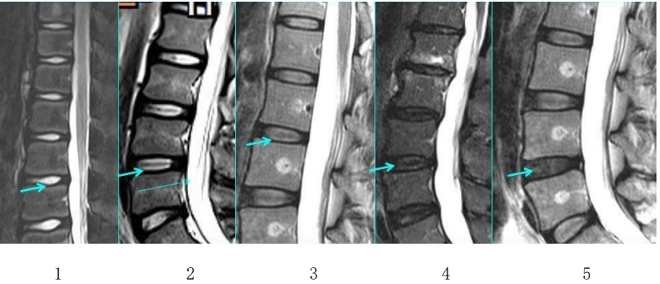

來!帶你快速了解腰椎間盤突出癥

來!帶你快速了解腰椎間盤突出癥來!帶你快速了解腰椎間盤突出癥01什么是腰椎間盤突出癥(簡稱腰脫癥)?腰椎間盤就像輪胎,外面一層是韌性較強的外胎,里面包裹著韌性較弱的內胎,均具有一定的彈性,可以緩沖吸收相鄰椎體之間的壓力。正常情況下,椎…查看詳情+